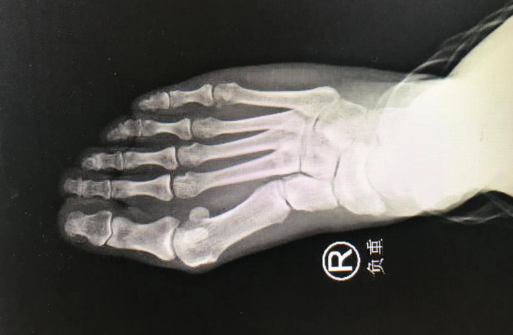

正好是足踝科曹广超主任坐诊,曹主任给王大姐做了仔细检查,又看了片子,发现其右足踇趾自趾跖关节向外偏斜移位,前足变宽,第1跖骨头内侧膨大,踇囊已经形成,局部红肿,一碰就痛,右足第1跖趾关节内侧、第2趾跖侧有轻度胼胝体形成,跖趾关节活动受限。诊断为双足踇外翻、右足踇囊炎。曹主任评估了一下,王大姐的右足踇外翻,可以通过微创手术矫正与解决疼痛。